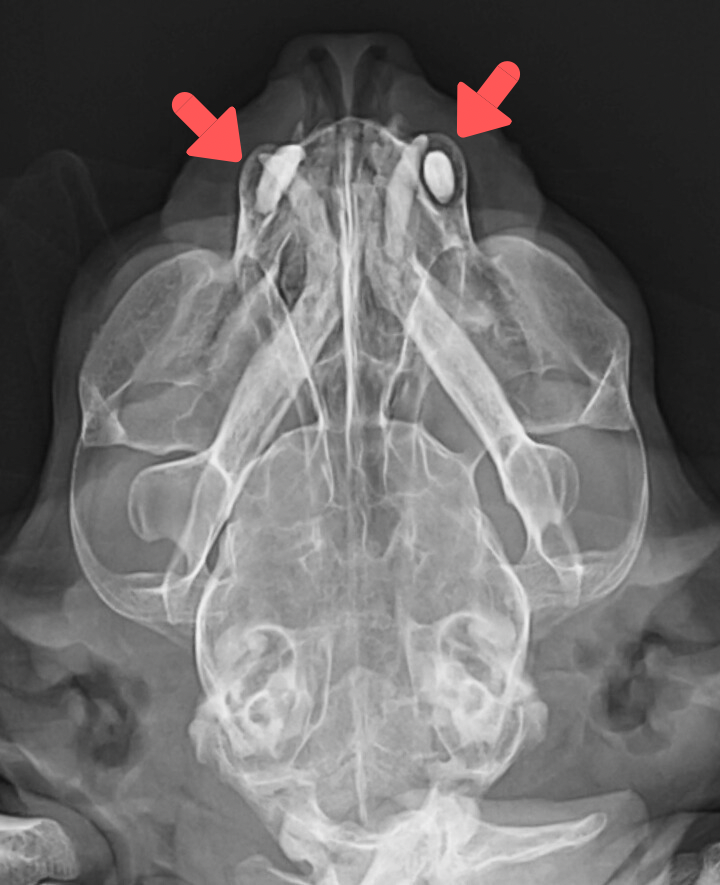

レントゲンでは、他に閉口障害の原因となるような顎の骨の骨折や脱臼などは認められませんでした。また、両側の犬歯の周りが黒く抜けており、歯周病であることがわかりました。

これは、歯の挺出(ていしゅつ)と言われる現象で、歯周病により歯を支える土台となる歯肉が弱くなって、歯が浮き上がるように前へ出てきてしまいます。